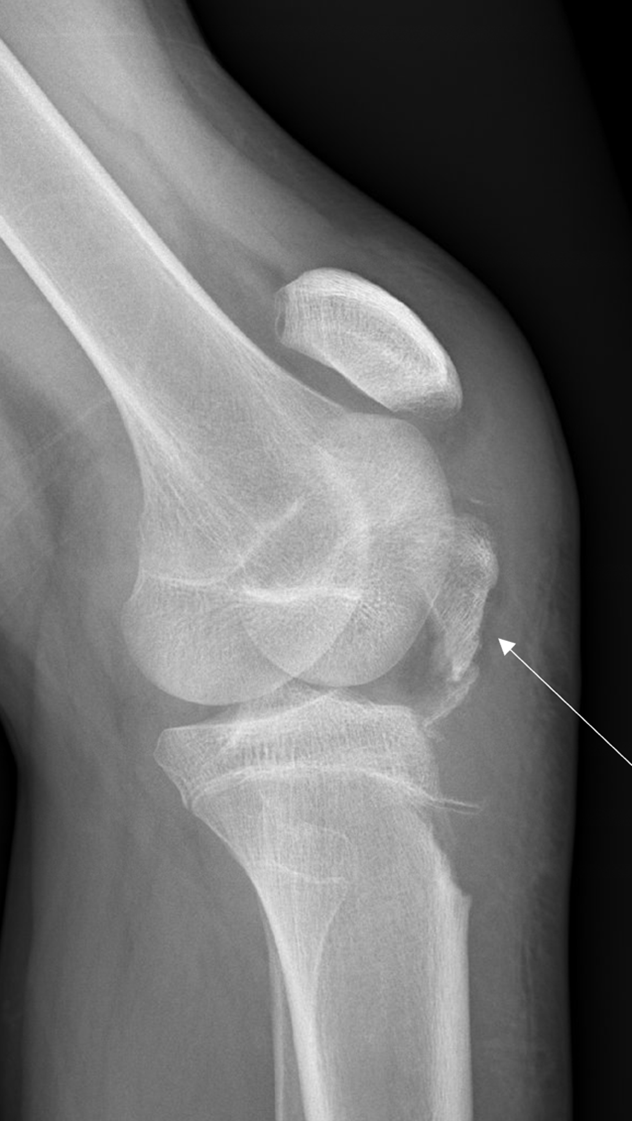

In our case report, we successfully identified key features suggestive of tibial tubercle fractures: disruption of the patellar tendon, posterior acoustic shadowing of a bone fragment, and a large joint effusion. To perform knee ultrasound, the linear probe should be used and placed inferior to the patella in sagittal plane. The patellar tendon should be visualized in two planes, fanning through it completely (Video 1), and compared to the contralateral normal knee. (Figure 4) Abnormal findings suggestive of epiphyseal fractures include disruption of the tendon, an increased hypoechoic space adjacent to or posterior to the tendon (suggestive of either hemarthrosis or a hematoma), or a hypoechoic zone (ie, posterior acoustic shadowing due to an avulsed bony fragment).3,4

Figure 4: A) Ruptured tendon (arrow) in comparison against (B) contralateral knee indicating the normal continuous tendon fibers (arrow)